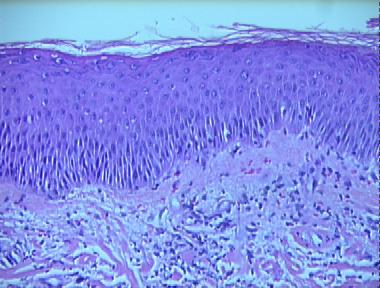

acute dermatophytosis

Histologic Features